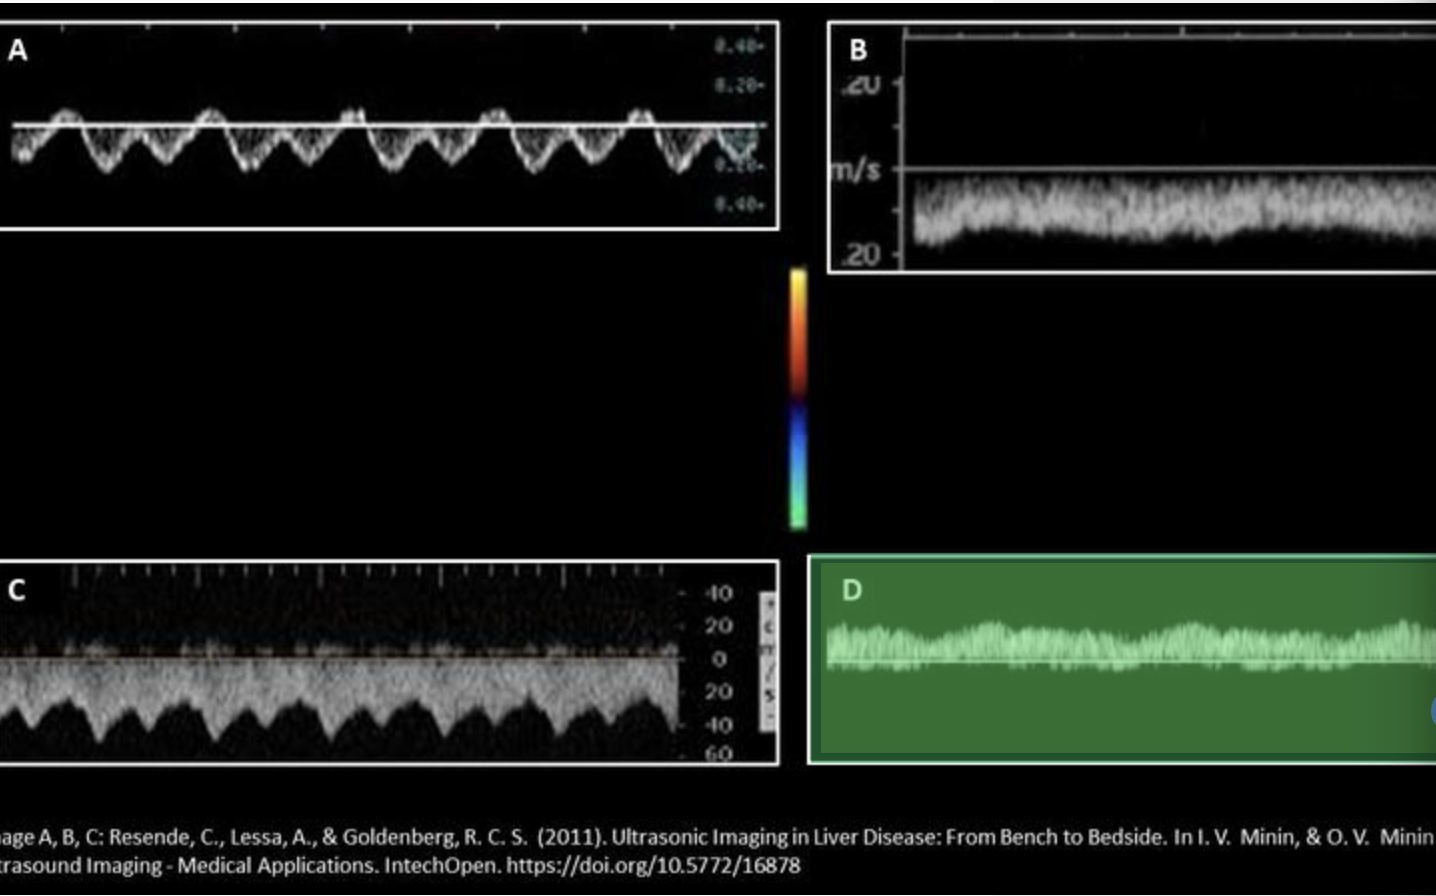

Which of the following terms can be used to describe the normal flow in the portal vein?

continuous |

Which waveform represents a normal portal vein waveform? Use your mouse to position your cursor over the correct waveform and click to set the answer.

***the color map displayed applies to all displayed Doppler tracings.

Normal hepatic venous flow will demonstrate:

Which waveform represents a normal inferior vena cava waveform? Use your mouse to position your cursor over the correct waveform and click to set the answer.

***the color map displayed applies to all displayed Doppler tracings.